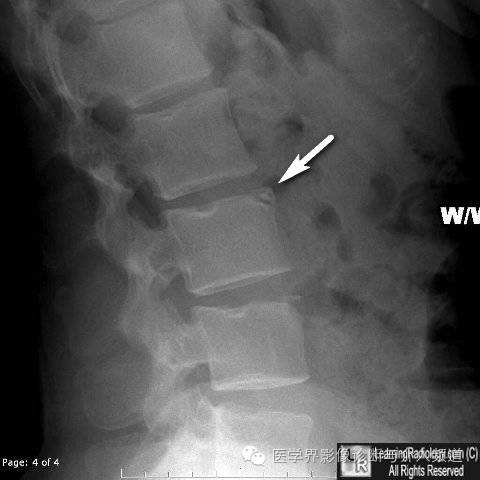

9、椎缘骨: 椎缘骨常见于椎体前上缘,表现为椎体前上角大小不一的三角形骨块,与椎体缺损区相对应,周边硬化。